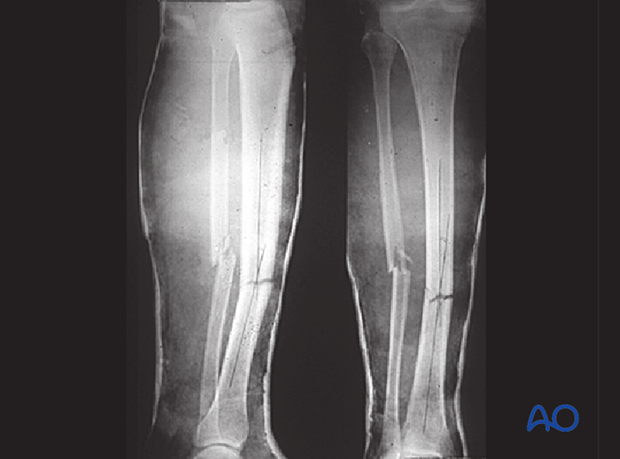

These x-rays show a simple transverse diaphyseal fracture of the tibia with an associated simple oblique fracture of the fibula. The treatment plan for this fracture is nonoperative.